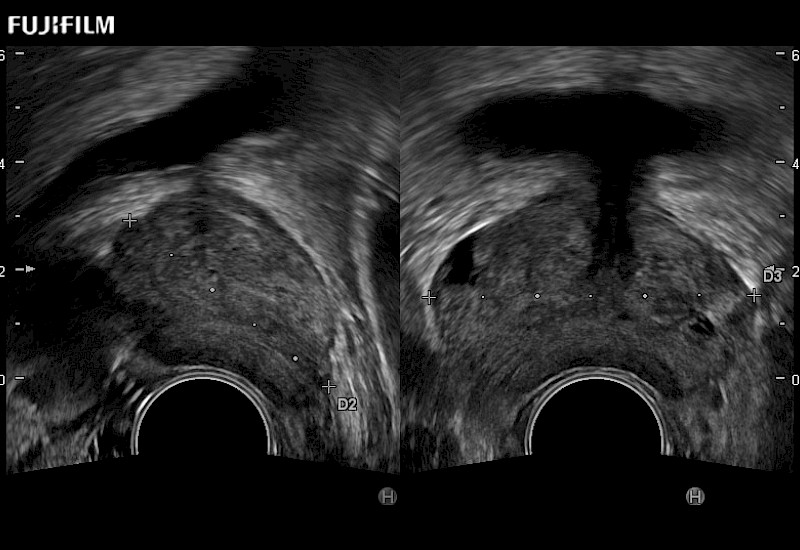

Exclusive 200° FOV end-fire prostate biopsy transducer.

Main Specifications:

Provides real-time imaging of both the sagittal and transverse planes